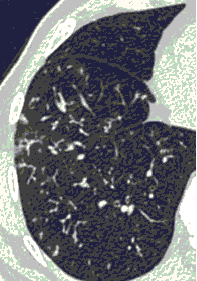

КТ имеет высокую чувствительность в выявлении изменений в легких, характерных для COVID-19. Применение КТ целесообразно для первичной оценки состояния ОГК у пациентов с тяжелыми прогрессирующими формами заболевания, а также для дифференциальной диагностики выявленных изменений и оценки динамики процесса. КТ позволяет выявить характерные изменения в легких у пациентов с COVID-19 еще до появления положительных лабораторных тестов на инфекцию с помощью МАНК. В то же время, КТ выявляет изменения легких у значительного числа пациентов с бессимптомной и легкой формами заболевания, которым не требуется госпитализация. Результаты КТ в этих случаях не влияют на тактику лечения и прогноз заболевания при наличии лабораторного подтверждения COVID-19. Поэтому массовое применение КТ для скрининга асимптомных и легких форм болезни не рекомендуется. При первичном обращении пациента с подозрением на COVID-19 рекомендуется назначать КТ только при наличии клинических и инструментальных признаков дыхательной недостаточности (SpO2 < 95%, ЧДД > 22).

4. Все выявляемые при лучевых исследованиях признаки, включая КТ-симптомы, не являются специфичными для какого-либо вида инфекции и не позволяют установить этиологический диагноз. Вне клинической (эпидемической) ситуации они не позволяют отнести выявленные изменения к пневмонии COVID-19 и дифференцировать их с другими пневмониями и невоспалительными заболеваниями. Данные лучевого исследования не заменяют результаты обследования на РНК SARS-CoV-2. Отсутствие изменений при КТ не исключает наличие COVID-19 и возможность развития пневмонии после проведения исследования.

15. Рекомендации по формированию описаний и оценке изменений в легких и ОГК при имеющейся/подозреваемой пневмонии COVID-19 представлены в Приложении 1.